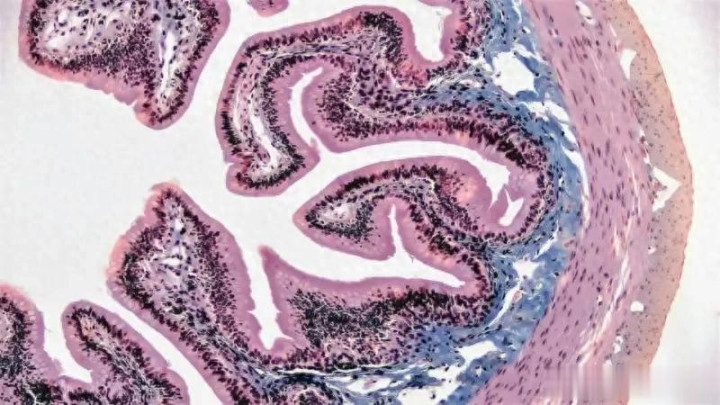

这项研究由栗田玲教授领导的团队完成,发表于《神经科学研究》杂志。团队借鉴聚合物物理学的原理,将tau蛋白的聚集过程比作高分子聚合物的结晶行为。在自然界中,聚合物不会直接从单体跃迁到晶体,而是先形成松散的“前体”结构,然后逐步有序化。同样,tau蛋白在阿尔茨海默病中并非直奔有害纤维,而是先聚集成直径数十纳米的柔性簇集。这些簇集像一团松散的线球,内部分子间作用力较弱,易于逆转。研究者使用小角X射线散射(SAXS)和荧光相关光谱等技术,首次在溶液中捕获这些瞬态结构。实验显示,这些簇集在肝素(一种人体天然抗凝血剂)存在下形成,但通过提高氯化钠浓度,就能屏蔽静电相互作用,将簇集瓦解。结果令人振奋:一旦前体簇消失,tau纤维几乎完全无法生成。

深入技术层面,tau前体簇的发现挑战了传统聚合模型。tau蛋白有六个亚型,分子量约40-70 kDa,在生理条件下呈无序构象。但磷酸化后,静电排斥减弱,促进簇集。栗田团队的SAXS数据量化了簇集尺寸:约20-50 nm,内部密度不均,类似于聚合物熔体中的浓度涨落。通过肝素诱导(肝素模拟细胞外基质负电荷),簇集形成速率与离子强度呈反比:氯化钠浓度升至0.5 mol/L时,簇集半衰期缩短至分钟级。这与聚合物结晶理论吻合:前体阶段受热力学驱动,可逆性高。未来,基于此的药物设计可聚焦小分子“簇集破坏剂”,如电荷屏蔽化合物或肝素类似物。挑战在于体内递送:脑血屏障是障碍,纳米载体或鼻腔喷雾或成解决方案。